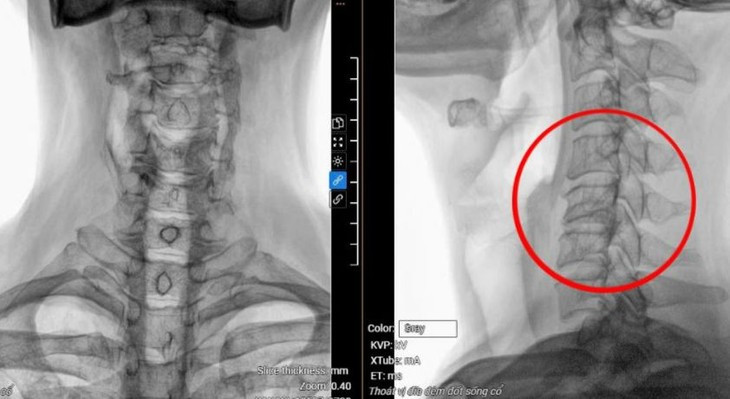

Kết quả chụp MRI 3 Tesla cho thấy bệnh nhân bị thoát vị đĩa đệm cột sống cổ nặng từ C3 đến C7, gù cột sống cổ, chèn ép làm tổn thương tủy C5, C6 (vị trí đốt sống cổ thứ 5 và thứ 6).

| Phim chụp MRI hiển thị vị trí đốt sống cổ bị thoát vị, tổn thương tủy của bệnh nhân. Ảnh BVCC |